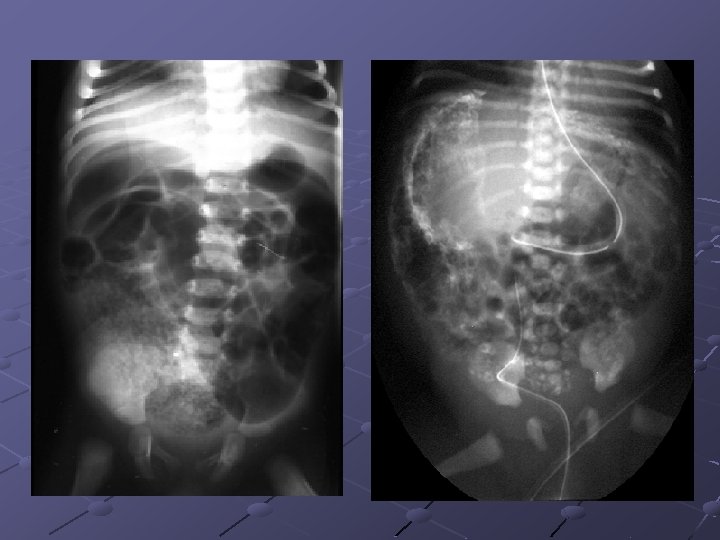

Cas n° 3 Garçon de 19 ans Pas d’antécédents particuliers Douleurs et distension abdominales, vomissements Examen distension diffuse, pas de signes de péritonite

« northern exposure sign » « coffee bean sign »

Volvulus du colon sigmoïde Cause fréquente de volvulus( segment long et mobile) ASP couché ( « coffee bean sign » ) pose le diagnostic dans 80% des cas Origine congénitale ou défaillance des moyens de fixité du colon ttt: décompression endoscopique suivie d’une résection élective